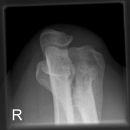

Ellenbogen a.p.

Patient sitzt seitlich am Tisch, Arm liegt ausgestreckt auf Kassette, Oberarm und Unterarm auf Schulterhöhe bringen, Hand in Supination, Handgelenk waagerecht.

Senkrecht auf Gelenk- und Filmmitte.

Freie Projektion des Gelenkspalts bei Fragestellung nach Frakturen, supracondyläre bzw. epicondyläre Kernauflösung bei Kindern. Wichtig: kann das Gelenk nicht gestreckt werden, müssen Unterarm und Oberarm getrennt aufliegend geröntgt werden, d.h. 2 Aufnahmen, bei Gips empfiehlt sich eine Radiusköpfchen- bzw. Processus coronoideus- Aufnahme bei 45°.

distale Humerunsanteile: Epikondylen, Capitulum humeri

proximale Unterarmanteile: Radius-Radiusköpfchen und -hals, Ulna -Schaft, Körper, Olecranon

Ellenbogengelenk vollständig a.p. orthograd abgebildet, Gelenkspalt in Filmmitte und überlagerungsfrei.